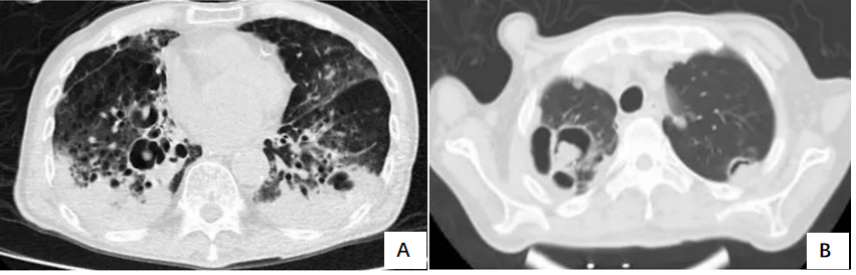

IAPA在发展过程中,较早可出现咳嗽、咳痰,进而出现呼吸困难、呼吸衰竭、缺氧性ARDS,进展迅速,即使气管插管、建立人工气道,患者也常出现气道峰压逐渐升高、潮气量逐渐下降,常因呼吸衰竭而无法挽救。但因其临床表现不特异,导致早期识别存在一定困难。(1)气管-支气管侵袭征象:沿支气管分布的结节及斑片影。对于没有基础疾病的重症流感病毒性肺炎患者,粒细胞数量正常,在曲霉感染后肺组织内会出现白细胞介导的强烈的炎症反应,导致渗出性支气管炎、支气管或肺泡受损及出血坏死,但直接侵袭血管的曲霉丝较少且主要以非增殖状态存在,因此多出现弥漫全肺的非特异性气道受侵型表现,而血管受侵型表现少见。如下图所示,第1天,支气管壁似乎有轻度增厚。病情进展至第4天,支气管壁明显增厚。随后迅速发展为支气管周围炎,并沿支气管侵袭、播散。图源:Respirol Case Rep, 2016, 4(1):32-34.注:双下肺实变,沿支气管血管束分布的实变、空洞,斑片状渗出影。注:支气管壁增厚、树芽征和沿着支气管血管束分布的实变。(2)对于免疫抑制宿主,可出现典型的曲霉感染影像学表现,例如实变与空洞伴晕征、空洞内有丝状结构及悬浮结节。注: A图见多叶肺炎和严重的小叶中心性、节旁性肺气肿; B图见右肺中叶空洞性浸润, 右肺下叶致密实变。图源:Chest, 2021, 160(2):e181-e184.注:A图可见实变、空洞,空洞内见丝状结构及悬浮结节;B图可见空洞、空气新月征。IAPA一种特殊的类型——侵袭性气管支气管炎,在支气管镜直视下可见气管和/或支气管溃疡、斑块或结节、假膜,是其典型表现。图源:国际呼吸杂志, 2023, 43(4):448-453.肺活检组织、气道斑块、假膜或溃疡的活检/刷检标本中发现真菌菌丝等特征性病理表现,可作为确诊标准。此外,在痰、支气管抽吸物、支气管肺泡灌洗液(BALF)中找到曲霉菌丝也可作为临床诊断标准。图源:Lancet Respir Med, 2018, 6(10):782-792.注:支气管活检组织病理显示有坏死物质和真菌成分,菌丝呈分枝状。图源:Chest, 2021, 160(2):e181-e184.图源:Tuberc Respir Dis (Seoul), 2014, 77(3):141-144.半乳甘露聚糖(galactomannan,GM)是曲霉特有的细胞壁多糖成分。菌丝生长时,半乳甘露聚糖是最早释放的抗原,是早期检测曲霉感染的经典方法。主要包括血清GM试验和BALF GM试验。血清GM试验在非粒细胞缺乏患者敏感性较低,仅为50%左右;ICU IPA患者的血清GM试验敏感性仅为30%~50%。在IAPA患者中,当以0.5作为GM试验阳性阈值时,诊断率仅20%。对于非中性粒细胞减少患者,BALF GM试验比血清GM试验具有更高的IPA诊断效率。EORTC/MSG标准采用1.0作为单份BALF阳性阈值的标准,当同时联合血浆/血清GM试验阳性时,BALF标本阈值可下调至0.8。我国学者研究发现,当截断值从0.5增加到0.717时,BALF GM试验可以显著降低假阳性率。无论是2016年美国传染病学会(IDSA)发表的《曲霉病诊断和管理实践指南》,还是2017年欧洲临床微生物学和感染病学会(ESCMID)/欧洲医学真菌学联盟(ECMM)/欧洲呼吸学会(ERS)联合发表的《曲霉病的诊断和管理指南》,都提及血清曲霉特异性IgG抗体在慢性肺曲霉病中有最高的检测阳性率。但2023年Clin Microbiol Infect杂志发表的一篇文章显示,IPA组的曲霉IgG抗体水平明显高于非IPA组。采样时间为发病后1~3个月内亚组显著高于采样时间为发病后<1个月亚组,影像学出现肺部空洞性病变亚组显著高于非肺部空洞性病变亚组。经过对比发现,曲霉IgG抗体的特异性和阳性预测值显著低于BALF GM。PCR的优势在于不仅能检测出曲霉的属和种,还可通过识别CYP51A基因突变来判断是否存在三唑类耐药可能。标本选择顺序:BALF>血浆>血清,但已进行了抗真菌治疗患者的血样本PCR阳性预测值可从62%降至5%。单份PCR阴性结果可极大程度地排除IPA可能。PCR可能更适合用于可疑IAPA患者在拟行抗真菌治疗前的筛查以及治疗过程中的实时监测。mNGS优势在于覆盖能力广, 时效性好, 不受先前使用抗菌药物的影响, 并可提供病原鉴定分型、耐药基因及毒力因子分析。但其检测成本较高, 结果需要临床医生进行解读和判断, 标本选择以BALF为最佳。